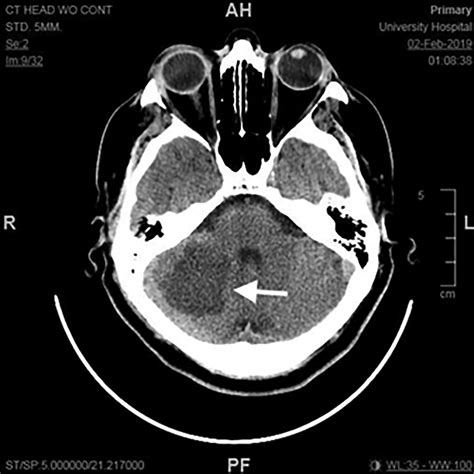

Advanced imaging is non-negotiable in these scenarios. While a CT scan is often the first line of defense, it can sometimes miss small cerebellar strokes. An MRI with Diffusion-Weighted Imaging (DWI) is the gold standard for detecting an ischemic stroke in the posterior fossa, as it can clearly distinguish between healthy and infarcted tissue even in the dense structures of the cerebellum.